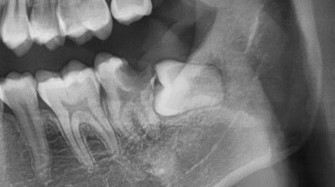

So I have this really bad molar cavity like its pretty much almost just 50% tooth now. I went to a private dentist and they said that it's barely on the edge of saveable - recommending an RCT quick.

I went to a government hospital to get a second opinion, they said that usually they would just remove the tooth, it's too much of a hassle at that point, because my wisdom tooth is still there and an RCT on that molar needs my wisdom tooth to be out of the way. I told them that I actually already had an appointment with the initial private dentist - scheduled a week after to remove the wisdom tooth. The government dentist said "oh, actually then maybe its doable, come back 2 weeks after the wisdom tooth is removed if that private dentist still says an RCT is doable."

A picture or x-ray would be more helpful to assess the restorability of the tooth.

I showed them the X-ray on my first visit. They kinda took a quick look and was like "okay, yeah that's pretty bad" but they do agree it is worth saving since I really wanted it saved.

Forgot to attach a pic

that's bad..... take that bugger out......

it does looks pretty bad, but seems like still restorable but pretty guarded prognosis.

One things for sure is that the impacted wisdom tooth needs to be removed first.